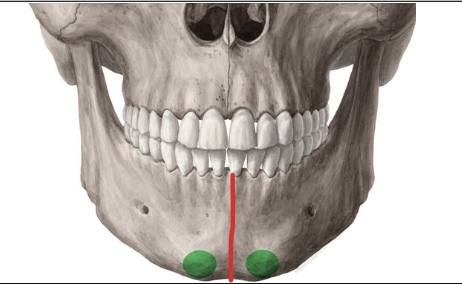

Sínfisis mentoniana

Articula los dos hemimaxilares inferiores

Eminencia mentoniana

Tubérculos mentonianos

Agujeros mentonianos